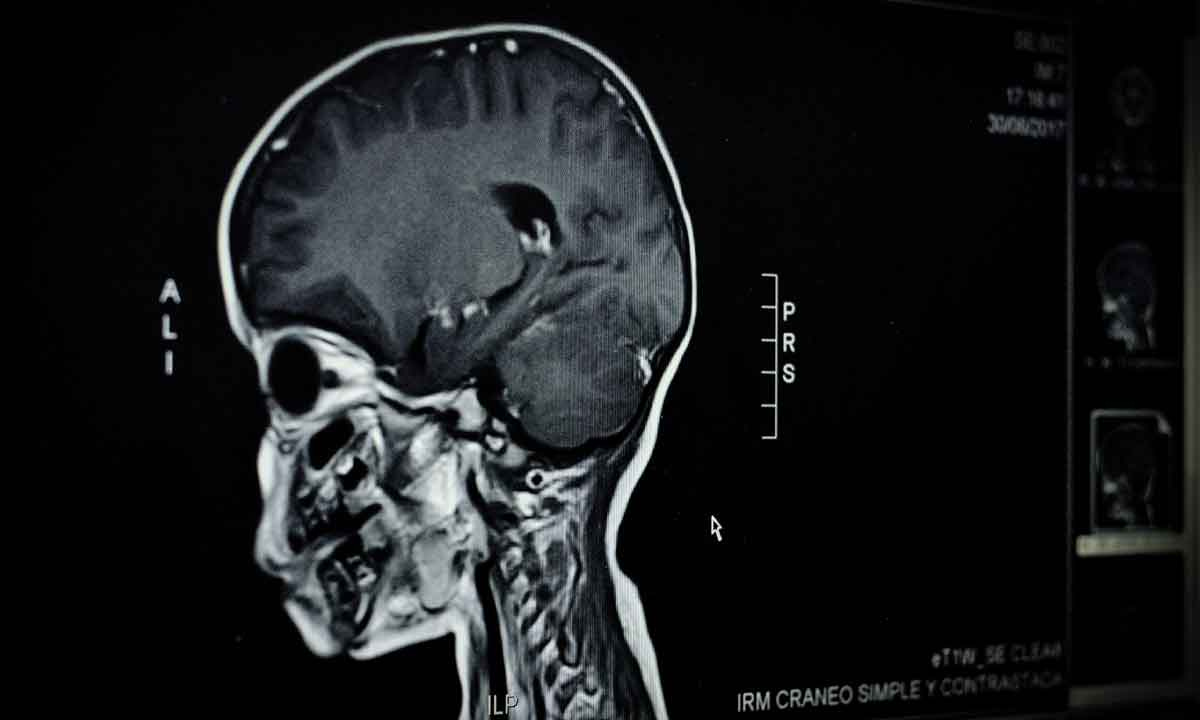

Klass points to the new Harvard research to underscore how early that “brain the child takes to school” begins developing. For years, a prevailing attitude has been that a child starts learning to read in pre-K or kindergarten. A longitudinal study by Gaab and her colleagues using MRI scans and an array of other assessments confirmed that the bases for reading skills begin to develop in the child’s brain by birth and continue building between infancy and preschool.

The study, “Longitudinal Trajectories of Brain Development from Infancy to School Age and Their Relationship with Literacy Development,” is the first to track brain development from infancy to childhood focused literacy skills — a window into later academic attainment.

Over a decade, Gaab and co-authors Ted Turesky, Elizabeth Escalante and Megan Loh conducted MRI brain scans of 130 study participants starting at 3 months old. Half of the children had a risk of dyslexia, with either an older sibling or one or both parents diagnosed with dyslexia, which can increase a child’s risk of reading challenges. For the first year of the study, the babies peacefully slept through the scan, tucked into the MRI machine wearing noise protection (“We got really good at putting other people’s babies to sleep,” Gaab said).

Babies are born with the raw material they need to hear, see, move and remember. The nerve fibers, or axons, that connect these disparate brain regions don’t grow automatically. They are cultivated by babies’ environments. MRIs of the participants as infants showed predictably smaller brains that appear more solid or smooth in the images. By the time the children were 5, the scans showed a robust network of branching pathways of these nerve fibers, said coauthor Turesky.

“The infant brain is very different compared to all other stages of life,” he said. “But if you look at the scan of a child at 5 years and then at 10 years, you can see there’s hardly any change in [those pathways]. Those early years are a time of very rapid growth.”

Though the human brain remains plastic and mutable for a lifetime, Turesky said, the scans underscore that earliest years are the busiest for building brain architecture — a fact that has important policy implications for early intervention and improved literacy curricula in preschools.